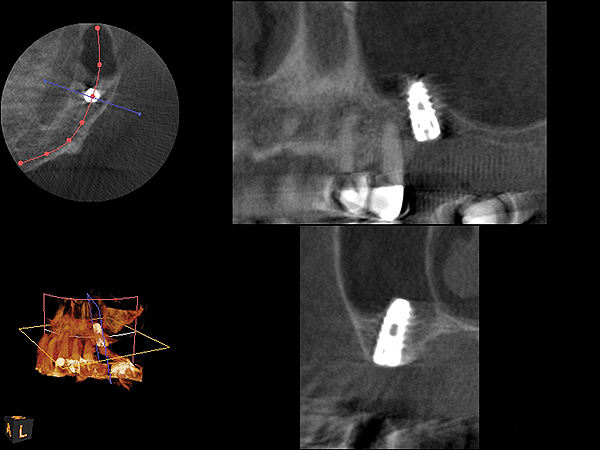

Fig 12. CBCT scan (Kodak 9000D) showing 3.5-month postoperative of implant No. 3 in place. Note homogenous appearance of the bone.

Figure 12

Fig 19. CBCT scan (Kodak 9000D) of implant No. 14 showing homogeneous appearance of the bone.

Figure 19

Fig 22. CBCT scan (Kodak 9000D) of No. 3 area, day of placement. Appearance of native bone and bone graft is clearly discernible.

Figure 22

The implant is then delivered and should be well stabilized in the bone. If there is any mobility of the implant, it can either be placed a little deeper (if there is enough native bone) or the implant can be removed and the procedure aborted, in which case it would be a two-stage procedure. This should rarely occur with the tapered designed implant, even with only 2 mm of native bone. Using a bone-level platform-shifting implant (or a tissue-level designed implant) is critical, as the hard and soft tissue will establish a biologic width. If an external hex type of implant is used and the shoulder is placed at the bone level, an expected bone loss of 1.5 mm to 2 mm will occur.24 Figure 10 shows proper bone-level implant depth placement with a platform-shifting design. In this case, a 3-mm healing abutment was placed at the time of surgery to avoid a secondary uncovering surgery, but an implant-level healing abutment could have been placed instead. As can be seen, there was only about 2 mm to 3 mm of native bone height. The membrane was raised about 8 mm to 9 mm. Comparing the radiograph on the day of surgery (Figure 10) to the 6-month postoperative radiograph (Figure 11) shows no loss of native bone, as well as the positive change in appearance of the grafted bone. The 3.5-month CBCT scan (Figure 12) shows good healing of the bone with no coronal bone loss. With minimal native bone present, as in this case, the use of a non-platform-shifting or non-tissue-level implant design could be problematic. After 1.5 mm to 2 mm of crestal bone loss, an external hex designed implant could develop instability with possible implant failure. If a non-tapered implant is used and bone loss occurs during healing, migration of the implant into the sinus could potentially occur. The surgeon can use either a healing abutment or implant-level closure screw over the implant shoulder. With patients who tend to use their tongues to explore or play with the area, or if the area is under a removable partial denture, a closure screw is recommended.

A 74-year-old male patient presented with about 4 mm to 5 mm of native bone in the No. 4 position (Figure 17). A composite graft, as described in Case 1, was used, as was the same implant type, but the implant was 11.5 mm in length with a taper of 5 mm to 4.2 mm. The approximately 16-month post-healed floor of the sinus was raised about 7 mm to 8 mm (Figure 18). The CBCT scan taken at 16 months postoperatively showed no change in appearance from the area of the old floor of the sinus to the new bone formed (Figure 19). Although it was endodontically involved, tooth No. 15 was not extracted, against professional advice. As can be seen in Figure 18, the No. 14 implant is acting as a bridge abutment.

This patient was a 73-year-old man with only about 3.5 mm of native bone in the No. 3 site (Figure 20). The composite graft used here was a 50:50 mixture of DFDBA and deproteinized bovine bone mineral (Osteohealth, www.osteohealth.com) with approximately 40% calcium sulfate added. The implant was the same type and length as in Case 1 above. Figure 21 shows the area on the day of placement. In the CBCT scan on the day of placement (Figure 22), the native bone and bone graft were clearly discernable. However, the postoperative radiograph taken at 6.5 months (Figure 23) showed no marginal bone loss and a significantly denser appearance than when the graft was place. The membrane was raised about 7 mm to 8 mm. The final radiograph was taken after extraction of tooth No. 2 and after extraction of tooth No. 4 and immediate implant placement.